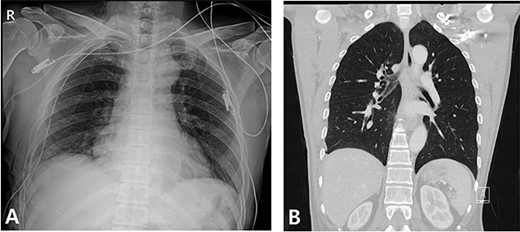

A 59-year-old man was admitted with multiple rib fractures and liver contusion due to a fall injury. He was standing on a chair for working at a farm, and it was knocked over causing him to fall and hit his flank against the corner of the chair. There was continuous pain while resting at the right flank and severe pain with pressure was noted, but no external wounds or bruises were observed. There were right 7th–11th rib fractures, scanty pneumothorax, minimal hemothorax and a 2-cm-sized liver contusion in abdomen and chest computed tomography (CT) scan (Fig. 1A, B). He was hospitalized for pain control and close observation in the general ward, and conservative management was initiated. Also, no significant changes were noted in the following daily follow-up chest radiographs. The patient suddenly complained of right-sided chest and back pain aggravation, cold sweating and fatigue 80 h after the traumatic injury. His mental status was alert, but v/s including systolic blood pressure (SBP) of 100–120 mmHg, heart rate (HR) of 40-60 beats/min and oxygen saturation of 100% during the admission changed to an SBP of 86/60 mmHg, HR of 88 beats/min and oxygen saturation of 97% when the symptoms occurred. Chest radiography was performed after the patient experienced aggravated symptoms, such as right-sided flank pain, cold sweating and fatigue. Compared to the previous scans, signs of increased opacification and peribronchial and parenchymal infiltrations were observed, which were indicative of hemothorax (Fig. 2A, B). We performed enhanced dynamic chest CT to identify any presence of active bleeding. On the chest CT scan, a large amount of hemothorax was identified in the right lung field along with multiple fractures of the right ribs. However, there were no signs of contrast leakage indicative of active bleeding (Fig. 3). Hemoglobin levels decreased from 13.1 g/dl on the day before the symptoms appeared to 11.5 g/dl at the onset of symptoms and to 9.4 g/dl after 2 h. Four packs of RBC transfusion and fluid were administered to the patient, and he was moved to the intensive care unit for close monitoring. And tube thoracostomy was performed, and 1600 ml of fresh blood was drained (Fig. 4A). The following day, 500 ml of blood was drained through the chest tube, but his v/s were stable (Fig. 4B). The amount of bleeding through the chest tube was decreased, but the drained fluid was fresh blood. And we thought that the remaining hematoma was not effectively drained, so the patient’s respiratory discomfort could persist and cause uneffective ventilation. And then we consulted with the Department of Thoracic Surgery, and video-assisted thoracoscopic surgery (VATS) exploratory thoracotomy was performed to identify the bleeding source caused by displaced rib and evacuate the large amount of hematoma. There was a large volume of hematoma within the pleural space and between the right lower lobe, diaphragm and fissure, but no active bleeding point was located. The fractured right 10th rib pierced through the pleural space and was displaced to the thoracic cavity, which was easily reduced. There was no injury surrounding the diaphragm, and although the general lung and chest wall contusions were severe, there were no signs of lung parenchymal lacerations (Fig. 5A–C). Chest tube drainage was serous, and there was no further bleeding. There were no signs of bleeding or any other abnormal findings on chest CT performed at the outpatient clinic, and the patient had no complaints of any symptoms (Fig. 6A, B).

Radiographic findings. (A) Day of symptoms, chest X-ray in the morning. (B) Chest X-ray after symptoms develop.